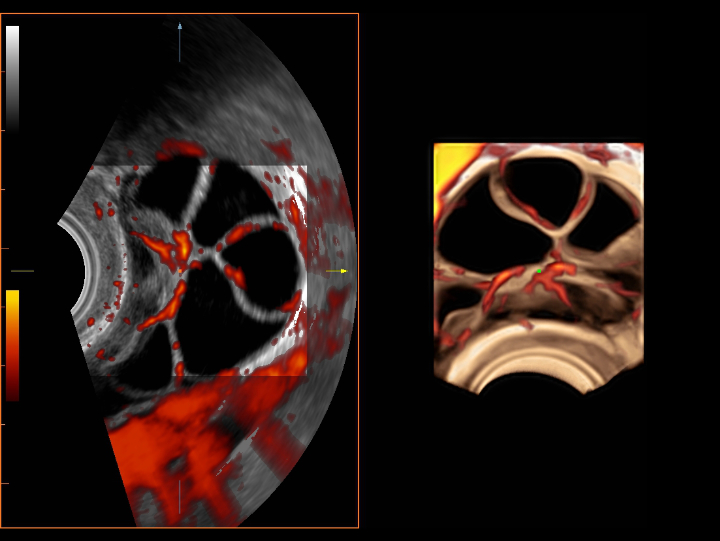

UWN+ CEUS provides excellence contrast agent sensitivity and image penetration to get more diagnosis information for gynecology tumor or other difficult diseases. Also MindrayŌĆÖs STE (Sound Trouch Elastogtaphy) can quantitatively evaluate tissue stiffness which is helpful for previse diagnosis of difficult uterus, cervix and ovary diseases.